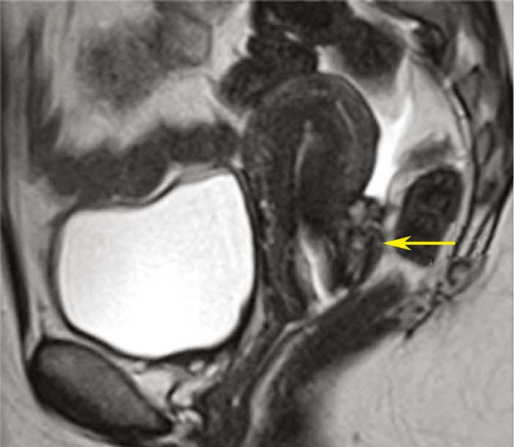

1.影像学检查 超声检查是诊断卵巢异位囊肿和膀胱、直肠内异症的重要方法,可确定异位囊肿位置、大小和形状,其诊断敏感性和特异性均在96%以上。囊肿呈圆形或椭圆形,与周围特别与子宫粘连,囊壁厚而粗糙,囊内有细小的絮状光点。因囊肿回声图像无特异性,不能单纯依靠B型超声图像确诊。盆腔CT及MRI对盆腔内异症有诊断价值,但费用昂贵,不作为初选的诊断方法。

子宫内膜异位症MR